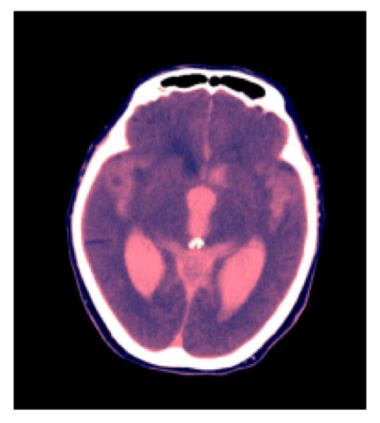

We present an effective method for Intracranial Hemorrhage Detection (IHD) which exceeds the performance of the winner solution in RSNA-IHD competition (2019). Meanwhile, our model only takes quarter parameters and ten percent FLOPs compared to the winner's solution. The IHD task needs to predict the hemorrhage category of each slice for the input brain CT. We review the top-5 solutions for the IHD competition held by the Radiological Society of North America(RSNA) in 2019. Nearly all the top solutions rely on 2D convolutional networks and sequential models (Bidirectional GRU or LSTM) to extract intra-slice and inter-slice features, respectively. All the top solutions enhance the performance by leveraging the model ensemble, and the model number varies from 7 to 31. In the past years, since much progress has been made in the computer vision regime especially Transformer-based models, we introduce the Transformer-based techniques to extract the features in both intra-slice and inter-slice views for IHD tasks. Additionally, a semi-supervised method is embedded into our workflow to further improve the performance. The code is available in the manuscript.

翻译:我们在RSNA-IHD竞争(2019年)中提出了一种有效的内爆出血检测方法(IHD),该方法超过了获胜者解决方案的绩效(RSNA-IHD 竞争(2019年),同时,我们的模型与获胜者解决方案相比,仅需要四分之一参数和10%的FLOP;国际HD的任务需要预测输入大脑CT的每个切片的出血类别。我们审查了北美辐射协会(RSNA)在2019年举办的IHD竞赛的5级顶级解决方案。几乎所有顶级解决方案都依靠2D共流网络和相继模型(双向GRU或LSTM)来提取虱内和肺间特征。所有顶级解决方案都通过利用模型共性能提高性能,而在过去几年中,模型数从7到31不等。由于计算机视觉系统,特别是以变压器为基础的模型取得了很大进展,因此我们采用了基于变压器的技术来提取IHDD任务的内切和相间观点的特征。此外,半超式方法已经嵌入我们的工作流程。